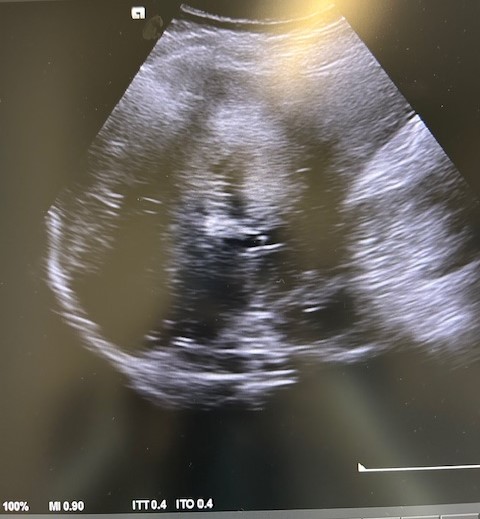

Descripción de los hallazgos ecográficos y las imágenes más relevantes para la resolución del caso

En la ecografía podemos apreciar hepatomegalia > 16 cm con múltiples imágenes en su interior hiperecogénicas sugestivas de LOE. No otros hallazgos a destacar.

El paciente fue valorado en Consultas Externas confirmando el diagnóstico. Se realiza ecografía abdominal con hallazgos de múltiples nódulos hepáticos de entre 12-35mm. En la colonoscopia, neoplasia circunferencial con aumento de consistencia, áreas ulceradas y necrosis, con estenosis incompleta, siendo compatible con adenocarcinoma de sigma.